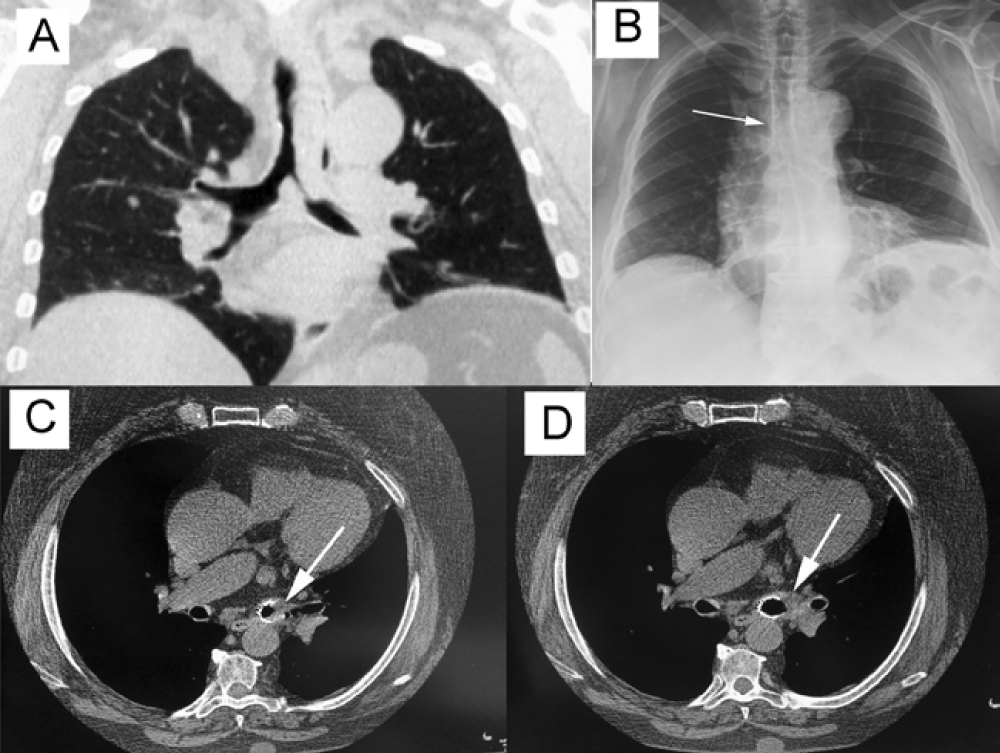

In May 2011, a 67-year-old woman without any past medical history was admitted to our hospital for increasing dyspnea and hemoptysis. On computed tomography severe tracheobronchial stenosis obstructing distal trachea and almost completely the main stem left bronchus was observed (Figure 1A). Endoscopy biopsy was suggestive of amyloidosis.

The mass was completely resected via rigid bronchoscopy. A Y-shaped covered, self-expandable metallic stent (SEMS) was then inserted to assure airway patency (Figure 1B).

Twelve months later, she returned to our attention because of recurrent pneumonia. An exophitic lesion within main stem left bronchus at distal end of stent was placed on CT scan (Figure 1C).

No complications were seen and the patient reported an improvement of respiratory function with patent left bronchus (Figure 1D). Seven months later, an endoscopic re-canalization was necessary to re-establish the airway patency owing to amyloid recurrence at the same site.